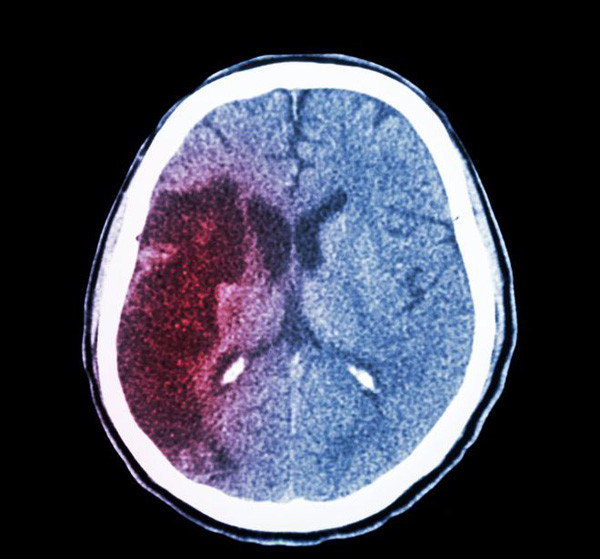

Xuất huyết não là một loại đột quỵ, hiện tượng xảy ra khi máu tràn vào mô não, gây tổn thương não. Khi máu từ tổn thương kích thích các mô não sẽ gây phù. Máu tụ lại làm tăng áp lực lên mô não gần đó, làm giảm lưu lượng máu, các tế bào không được nuôi dưỡng sẽ bị chết, vỡ mạch. (Ảnh minh họa)